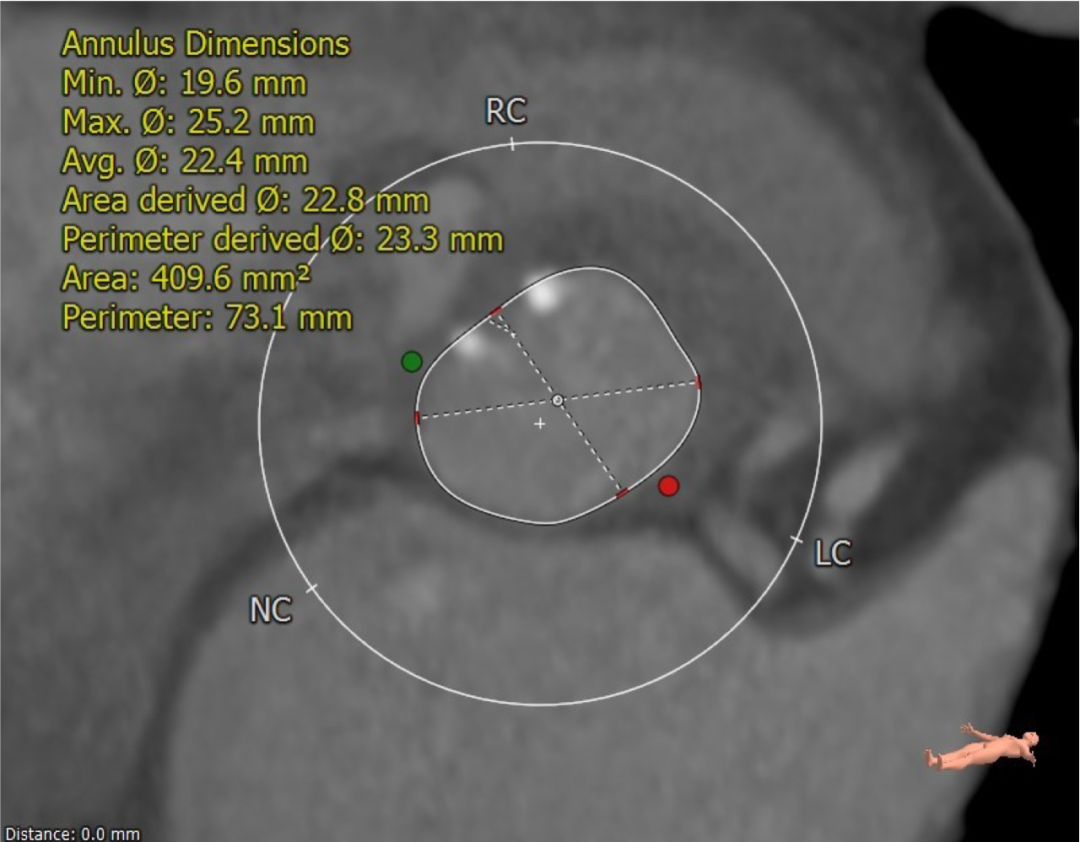

CT分析结果

该名患者为Type 0型二叶瓣,钙化分布不对称,瓣叶有轻度增厚。瓣环最短径为19.6mm,最长径为25.2mm,平均瓣环直径为22.4mm。左冠开口高度15.6mm,右冠开口高度15.9mm。

瓣环